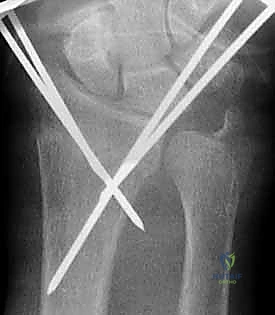

4. إدخال الأسلاك المعدنية (Pinning)

باستخدام مثقاب جراحي كهربائي دقيق، يقوم الدكتور هطيف بإدخال السلك المعدني الأول عبر الجلد، مروراً بالعظم السليم، ثم يعبر خط الكسر ليصل إلى الشظية المكسورة ويثبتها.

هناك عدة تقنيات هندسية لإدخال الأسلاك، أشهرها:

* التثبيت المتقاطع (Cross-Pinning): إدخال سلكين من زوايا مختلفة ليتقاطعا داخل العظم، مما يوفر ثباتاً دورانياً ممتازاً.